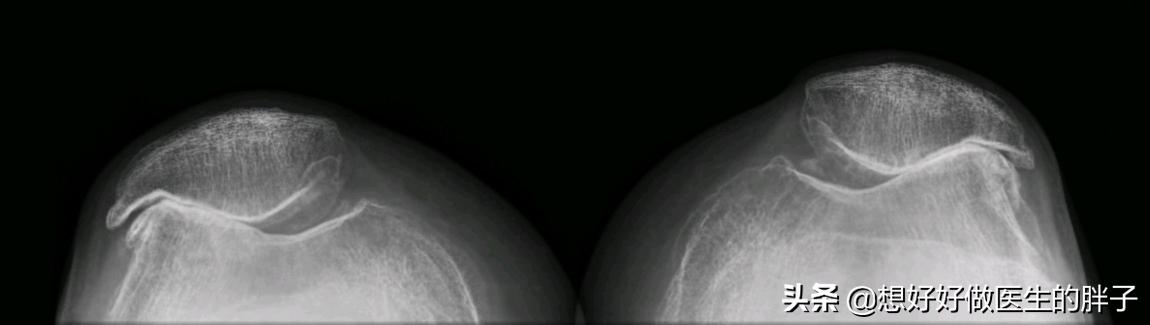

●当软骨磨损发展到中期,软骨可能已经发生了碎裂,甚至有部分软骨发生了脱落,那么此时在核磁上影像结果是比较清晰的,但是在x线上可能会没有异常,因为在x线上我们无法发现软骨的改变。所以在这个时候往往结合患者的症状查体以及核磁检查,可以做出明确的诊断。

●当软骨磨损特别严重,患者疼痛比较明显的时候,就没有必要浪费金钱进行核磁检查了,因为此时因为软骨磨损的特别严重,髌骨以及后方的股骨关节间隙已经出现了明显的狭窄,而且形态已经发生了明显的改变,做普通x线检查就可以明确问题了。